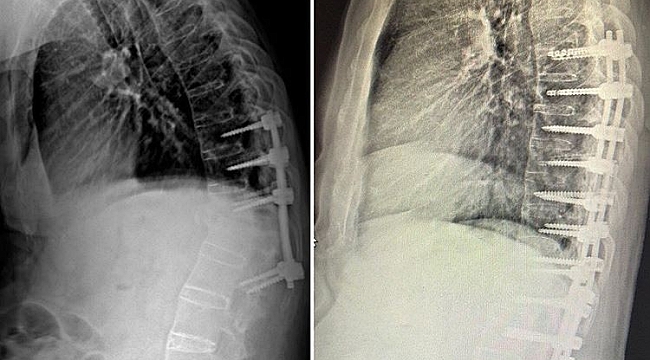

Manisa Şehir Hastanesi Beyin ve Sinir Cerrahi Kliniğinde skolyoz ve kifoz ameliyatları başarı ile gerçekleştirilmeye başladı. Manisa'da M.E. (63) isimli yaşlı adam 6 ay önce geçirdiği trafik kazası sonrası omurgasında oluşan kırıklar nedeniyle başka bir şehirde ameliyat oldu. Aradan geçen 6 ay içinde yaşlı adamın omurgasında öne doğru kamburluk, solunum sıkıntısı ve yürüme bozukluğu başladı. Manisa Şehir Hastanesine müracaat eden yaşlı adam yapılan tetkiklerin ardından Beyin ve Sinir Cerrahi Hekimi Op. Dr. Ülkün Ünlü Ünsal tarafından ankilozan spondilit tanısı ile ameliyata alındı. Yapılan başarılı operasyonun ardından yaşlı adamın hem kamburluğu giderildi hem de yeniden sağlığına kavuştu.

Ameliyat hakkında bilgi veren Manisa Şehir Hastanesi Beyin ve Sinir Cerrahi Hekimi Op. Dr. Ülkün Ünlü Ünsal, "M.E. 63 yaşında ve halk arasında Ahmet Mete Işıkara Hastalığı olarak da bilinen Ankilozan Spondilit tanılı hastamız, 6 ay önce geçirmiş olduğu trafik kazası sonrası omurgasında T12-L1 kırık oluşmuş ve dış merkezde ameliyatı gerçekleştirilmiş. Aylar içinde omurgasında öne doğru oluşan kamburluk (kifoz) meydana gelmiş. Omurgasındaki eğrilik nedeni ile duruş bozukluğuna bağlı solunum sıkıntısı ve yürüme bozukluğu yaşamaya başlayan hasta M.E. Manisa Şehir Hastanesi Beyin ve Sinir Cerrahi Kliniğine başvurmuş gerekli tetkikleri yapılmış, gerçekleştirilen başarılı ameliyat sonucunda omurgasındaki eğrilik giderilerek sağlığına kavuşmuştur. Hastanemizde cerrahi tedavi olarak omurga tespit sistemleri ve ameliyatları ücretsiz olarak yapılmaktadır" dedi.